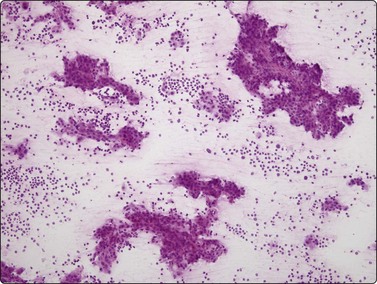

Fig. 10.2 Hepatocyte reactive changes

(A) Cells showing decreased cohesion, anisokaryosis and well-defined cell borders; note the scattered Kuppfer cells and lymphocytes (Pap, IP); (B) A sheet of cells showing mild disorganization and prominent nucleoli (H&E, HP).

Fig. 10.3 Cirrhosis

Poorly cohesive hepatocytes with degenerative/regenerative features; a sheet of small cohesive bile duct cells; note several Kupffer cells (arrow) (MGG, HP).

The presence of parenchymal disease is indicated by decreased cohesion of hepatocytes. Smears may be hypercellular and appear quite pleomorphic due to anisocytosis. The hepatocytes are swollen to a variable degree, and the cytoplasm stains less uniformly than usual, paler at the periphery of the cell. Cell membranes which are indistinct in normal hepatocytes become more clearly visible (Fig. 10.2A). Fatty change is commonly seen as intracytoplasmic vacuoles of variable size displacing the nucleus to the periphery. Despite nuclear pleomorphism and binucleation, the chromatin pattern remains finely granular. Intranuclear cytoplasmic invaginations are seen in some nuclei, large prominent nucleoli in others (Fig. 10.2B). There are no atypical bare hepatocyte nuclei in the background. Liver cell necrosis may be obvious in severe disease. Acidophilic bodies and alcoholic hyaline are difficult to identify in cytological preparations.12,75 The number of lymphocytes and of Kupffer cells is increased. The Kupffer cells often appear swollen and may cluster. The number of sheets of bile duct epithelium is often increased, particularly in cirrhosis (Fig. 10.3).

The degree of parenchymal abnormality varies widely. The reactive change commonly seen adjacent to a neoplasm is an example of mild change, including some dissociation and swelling of hepatocytes and mild to moderate anisokaryosis. In cirrhosis, which may mimic neoplasia radiologically as well as cytologically,76 there is a marked increase in the number of Kupffer cells and of bile duct epithelial cells, fatty change, and dissociation of hepatocytes. Bile stasis is easily recognized as casts of dense material between hepatocytes, staining black–green with MGG (Fig. 10.4), yellow–green with Pap or H&E. Nuclear changes and nucleolar enlargement may be quite prominent. In so-called liver cell dysplasia associated with cirrhosis, there is a dominant background of normal hepatocytes among which are scattered atypical cells with considerably enlarged nuclei. The fibrosis of cirrhosis is not often evident on routinely stained smears, but can be demonstrated on smears or on cell block material using a connective tissue stain. Normal liver will demonstrate a fine regular network of reticulin. Cirrhosis is characterized by a disorganized but still intact network (Fig. 10.5). HCC typically shows fragmentation or a complete absence of reticulin framework.77,78